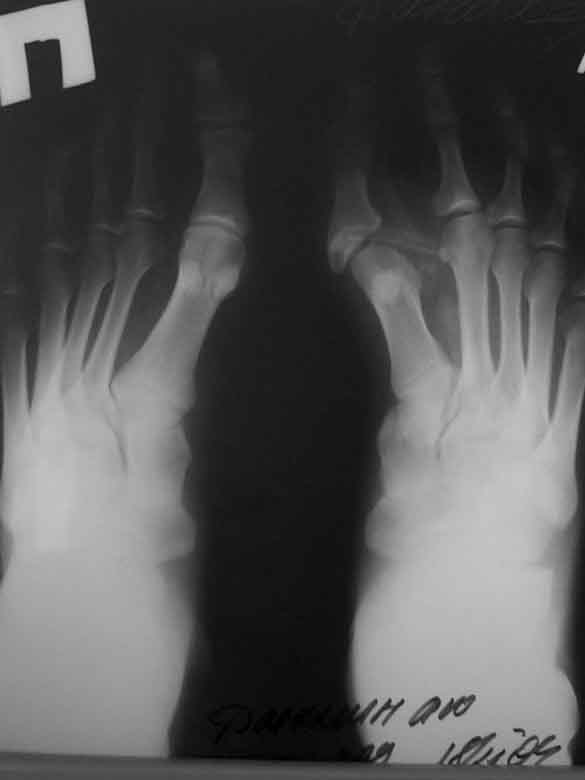

Re: Аномалия 1 п стопы

Прилагаю послеоперационные рентгенограммы.

Планирнуем использовать приводящуюю шину для 1 п.

Вопрос о проведении реконстрнуктивных операций на костях поднимем при наличии жалоб.